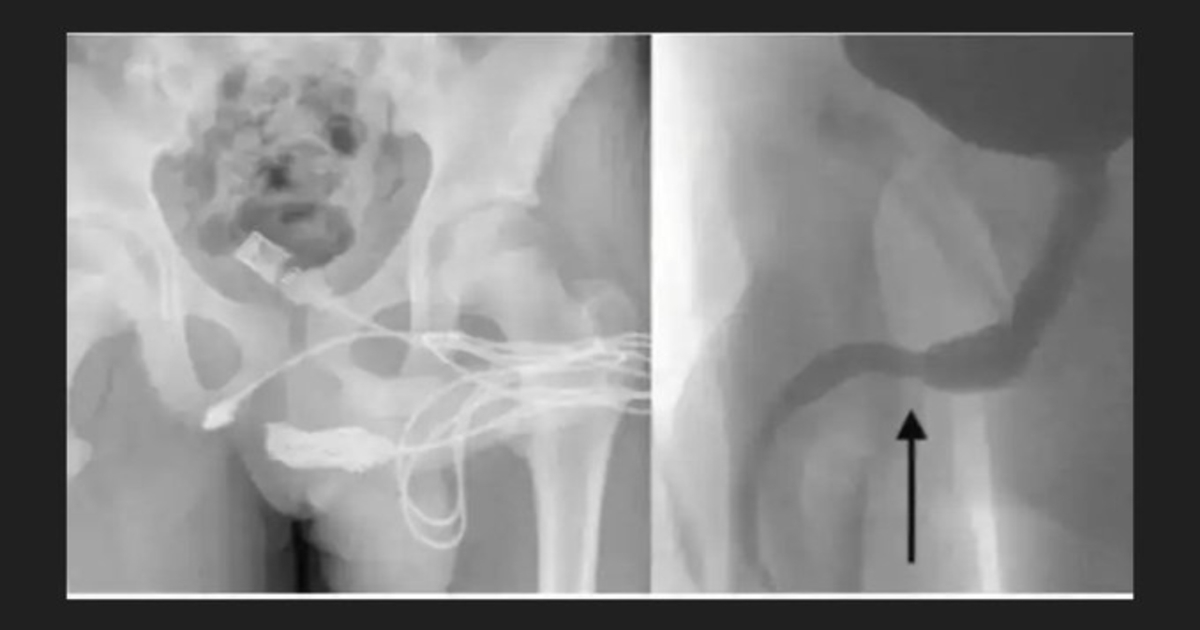

இதையடுத்து, அவனை அவசரமாக மருத்துவமனைக்கு கொண்டு சென்றனர். எக்ஸ்ரே பரிசோதனையில் வயர் உள்ளே சிக்கியிருந்த விதம் மருத்துவர்களையே அதிர்ச்சியடையச் செய்தது. சாதாரண முறையில் அதை அகற்ற முடியாது என உறுதியானதால், உடனடி அறுவை சிகிச்சை மேற்கொள்ளப்பட்டது. அந்தரங்க உறுப்புக்கும் மலக்குடலுக்கும் இடைப்பட்ட பகுதியில் துளையிட்டு, பல மணி நேர முயற்சிக்குப் பிறகே வயர் வெளியே எடுக்கப்பட்டது.